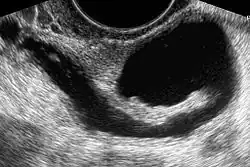

| The presence of a hydrosalpinx by sonography indicates distal tubal obstruction | |

While a full testing of tubal functions in patients with infertility is not possible, testing of tubal patency is feasible. A hysterosalpingogram will demonstrate that tubes are open when the radioopaque dye spills into the abdominal cavity. Sonography can demonstrate tubal abnormalities such as a hydrosalpinx indicative of tubal occlusion. During surgery, typically laparoscopy, the status of the tubes can be inspected and a dye such as methylene blue can be injected in a process termed chromotubation into the uterus and shown to pass through the tubes when the cervix is occluded. Laparoscopic chromotubation has been described as the gold standard of tubal evaluation.[3] As tubal disease is often related to Chlamydia infection, testing for Chlamydia antibodies has become a cost-effective screening device for tubal pathology.[3]

While IVF therapy has largely replaced tubal surgery in the treatment of infertility, the presence of hydrosalpinx is a detriment to IVF success.[5] It has been recommended that prior to IVF, laparoscopic surgery should be done to either block or remove hydrosalpinges.[11]